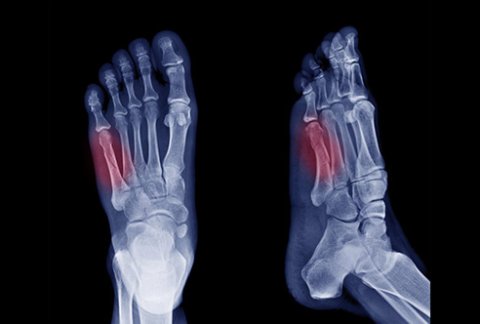

The 5 most common fractures around the foot and ankle

Fractures, or broken bones, are common and temporary debilitating injuries. However, ...

What is bone a fracture and how long does it take to heal?

A bone fracture occurs when there is a break or a ...